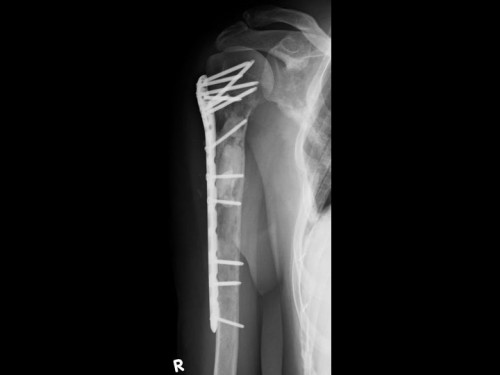

63-jährige Patientin. Bei ihr ist ein operiertes Mammakarzinom vor 3 Jahren bekannt. Das Ausgangsstumorstadium war: pT2, pN 0/1 (sn), L0, V0, cM0, R0, G2. Aktuell plagen sie Schmerzen in der rechten Schulter, die insbesondere bei Bewegung auftreten. Ein Trauma hat nicht stattgefunden.

Untersuchungsbefund der rechten oberen Extremität:

- Weichteilschwellung und Druckschmerz über Schulter und proximalem Oberarm

- Aktive Beweglichkeit des Schultergelenkes schmerzbedingt erheblich eingeschränkt